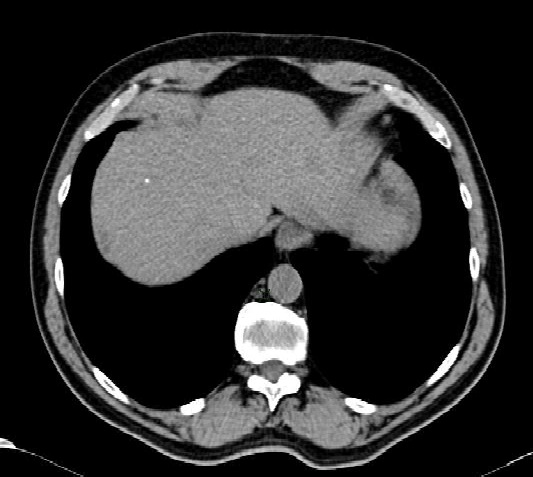

影像学在肝癌诊治过程中的角色: 1. 发现病变:我们究竟在多大程度上可以发现早期肝癌。 2. 对发现的病变进行鉴别诊断:我们究竟发现的是不是肝癌 3. 对病变进行分期:如果是肝癌,究竟到了什么程度,和预后的关系如何 4. 疗效判定:有效评价肝癌治疗后影像判定的标准是什么 5. 肝移植患者的评估:在等候肝移植的患者中,如何通过影像学判定他们的优先权 6. 肝功能的测定:通过影像学判定一个器官的功能储备状态,于肝脏还是个难题。 一、肝癌病变的发现 肝癌早期病变发现的意义在于不管对于肝切除,还是局部介入治疗都比晚期肝癌预后要明显好,甚至可能增加治愈的机会。对于肝移植候选者优先权的判定也是非常重要的。所谓肝癌病变的发现有两个问题,首先以目前现代化的影像学手段究竟在多大程度上能够发现早期肝癌;其次,以目前现代化的影像学手段监测高危人群(慢性肝炎病毒携带者,肝硬化患者)的结果如何,换句话说这样的方法究竟在多大程度上发现早期肝癌。 目前早期肝癌的诊断方法包括: 1. 超声:首选,或筛查;多数情况下为低回声结节,也有高回声,等回声或混合回声病变。 2. 增强的多期CT:属于二线检查,当甲胎蛋白升高或/和出现超声怀疑的结节。

3. 动态增强MRI:倾向应用于合作的病人,检查结果更精确。在平扫T1,结节为高信号、低信号或等信号;在T2为高信号,虽然比较可靠,但不敏感。弥散成像取决于分化程度(differenciation)。出现脂肪高度提示,因为增生结节含有脂肪出现。 4. 动态肝特异性造影剂增强MRI 5. CT 动门脉造影 6. 活检 由于现代医学影像学的进步,大肝癌是非常容易被发现。这里所指肝癌病变的发现主要是指肝癌早期病变的发现。所谓早期病变,指病变为小肝癌或早期肝癌。关于早期肝癌的定义目前尚无统一标准,我国标准为直径小于3cm 或两个相邻结节直径之和小于3cm,大于2cm的HCC常有包膜。小肝癌的发现远非人们想象的乐观,特别是极小肝癌是肝癌影像诊断中的难点。 只有通过影像学和病理对照我们才能够得出小肝癌影像诊断的精确性,换句话说影像学检查小肝癌对比金标准是病理。肝移植患者被切除肝脏的病理检查与术前的肝影像学对比研究可以为我们提供可比较的数据。 Maluf 等人报告,切除肝脏病理检查所示,术前被影像学检查丢失的HCC占36.4%[5]。即使用最现代的多排CT技术,并且采用精细的多期影像采集方式丢掉肝癌的几率仍为11%,如果需要典型的影像学表现来诊断HCC的情况下,CT的敏感性下降到43%[6]。相似情况,<2cm 结节,MRI的敏感性下降到85%,达到确诊的仅有62%的病例[7]。很明显,在末期肝硬化病人任何影像手段诊断肝癌的精确性是很差的[8~10]。 意识到肝硬化和病毒性肝炎与肝癌发生之间的关系,就建立了基于超声和甲胎蛋白测量的高危人群(东方)和肝移植候选者(西方)普查或筛查的策略。各国末期肝硬化病人监测建议也非常不同[11~13]。究竟多长的时间间隔进行一次监测检查?缺少对照研究。有关这一议题的共识还不存在,因此需要更多的数据,特别是证明由于严重的肝功能失代偿肝移植候选者哪一种影像学手段是理想的。必须记住所有的影像学技术对极小的结节的敏感性较差。 有关这一所谓监测建议应该来自不同时间间隔或不同影像诊断方式的随机对照研究。 Trinchet等人[14]多中心随机比较两个高危人群的检查周期:6个月 vs 3个月。直径≤3cm肝癌为主要研究目标。43个医学中心收集1278例病人(随机分配 3月组 N=640;6月组 N=638),最终发现至少一个病灶的病例为358例(28%),确定为肝癌仅有123例(9.6%)(单结节 58.5%,≤3cm 74%)。局灶性病变发生率在3月组和6月组之间没有明显差异(2年评估,20.4% 和 13.2%,P =0.067)但是,≤10mm的病变增加(3月组,41%,6月组28%; P = 0.002)。随机分组之间肝癌的发生率(P =0.13)或直径小于3cm肿瘤(79% vs 70% P =0.30)的发病率没有统计学意义。换句话说,尽管每3个月进行高危人群的超声筛查可以比每6个月发现更多的小的局灶性结节,但并没有改善小肝癌的发现率。改文献甚至对比了3月组和6月组的治疗后5年的生存率,分别为84.9%和85.8%(P =0.38)下图